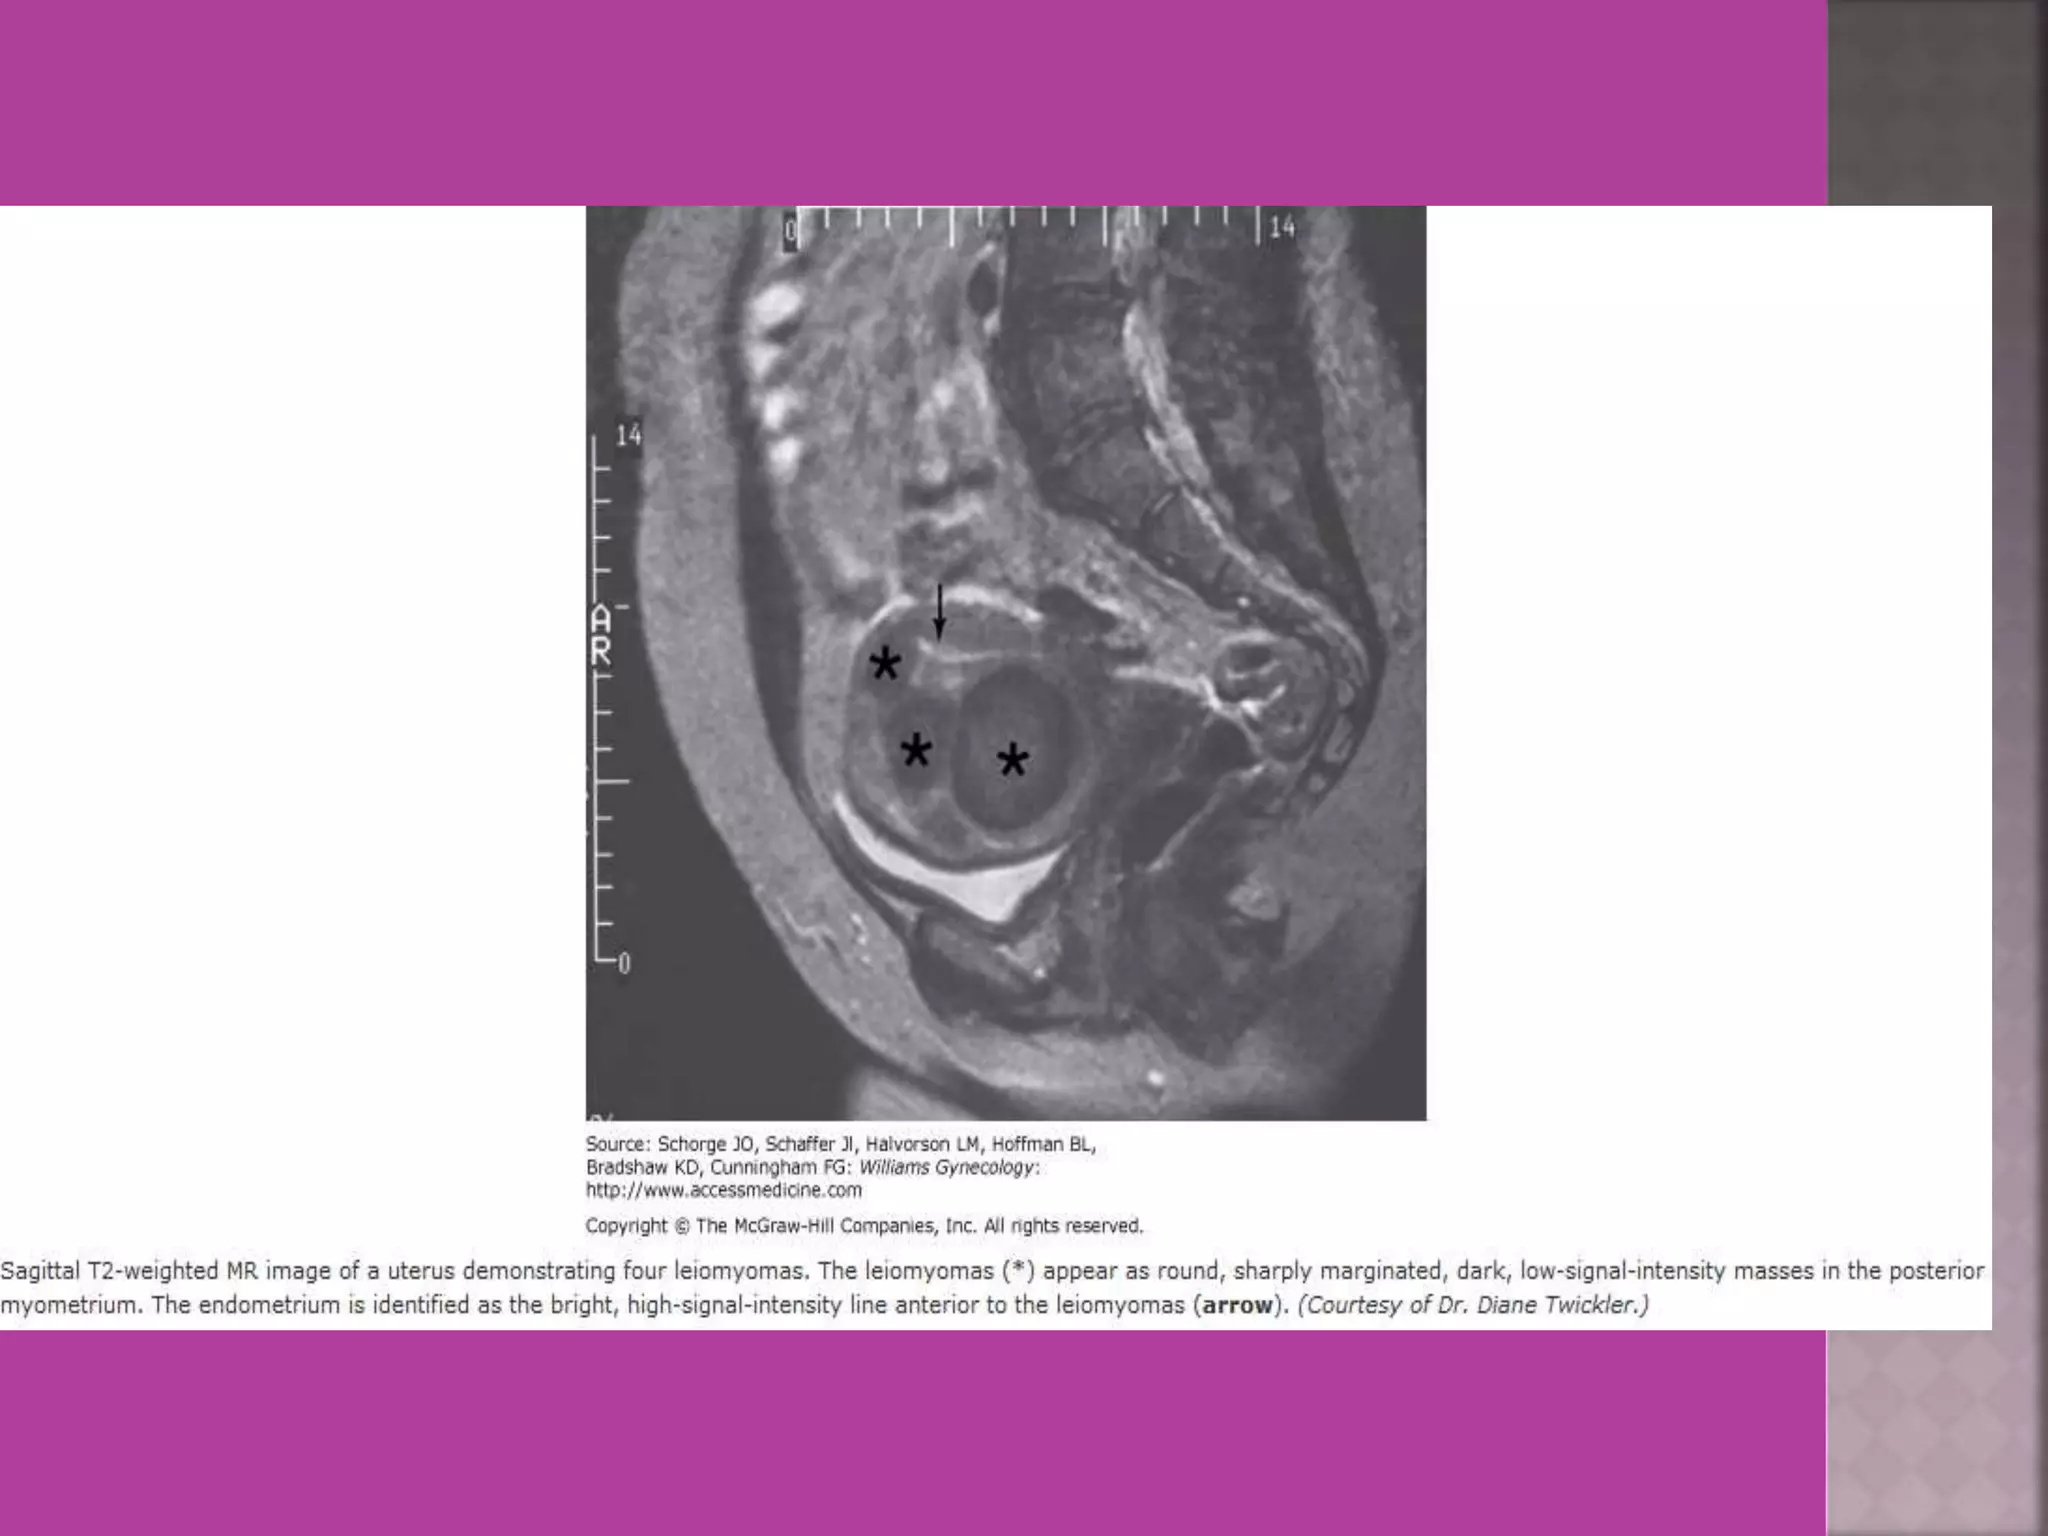

 Myoma—to differentiate myoma from

adenomyoma.localization of myoma—sub

serous/ intra mural or sub mucous.